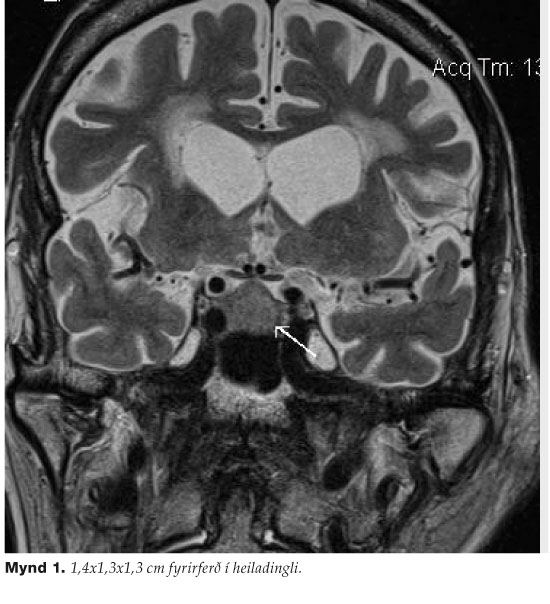

Sterkur grunur vaknaði um sjúkdóm í heiladingli sem ylli skertri framleiðslu heiladingulshormóns. Segul---ómun af tyrkjasöðli (mynd 1) sýndi 1,4 x 1,3 x 1,3 cm fyrirferð í heiladingli sem óx upp að sjóntaugavíxlum (chiasma opticum) og innri hálsslagæð hægra megin. Sjónsviðsmæling sýndi væga skerðingu gagnaugamegin á vinstri hlið. Útlitið var talið samrýmast góðkynja kirtilæxli í heiladingli. Eftir samráð við heilaskurðlækna var ákveðið að bíða með skurðaðgerð og endurmeta æxlið þremur mánuðum síðar.